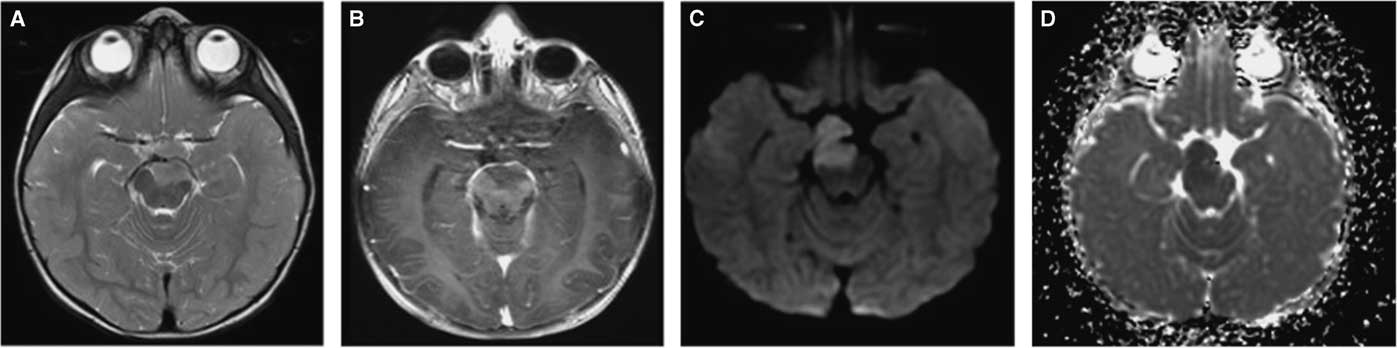

Figure 3 MRI of the pontomesencephalic junction showing the space occupying lesion measuring: 1.5×2×2 cm in each plane and extending into the interpeduncular fossa. It is isointense to the cerebral cortex in the T2 sequence (A) and has marked restriction diffusion as can be seen by the hyperintense DWI (C) and hypointense ADC map (D). There is no contrast enhancement (B). There is no significant mass effect.